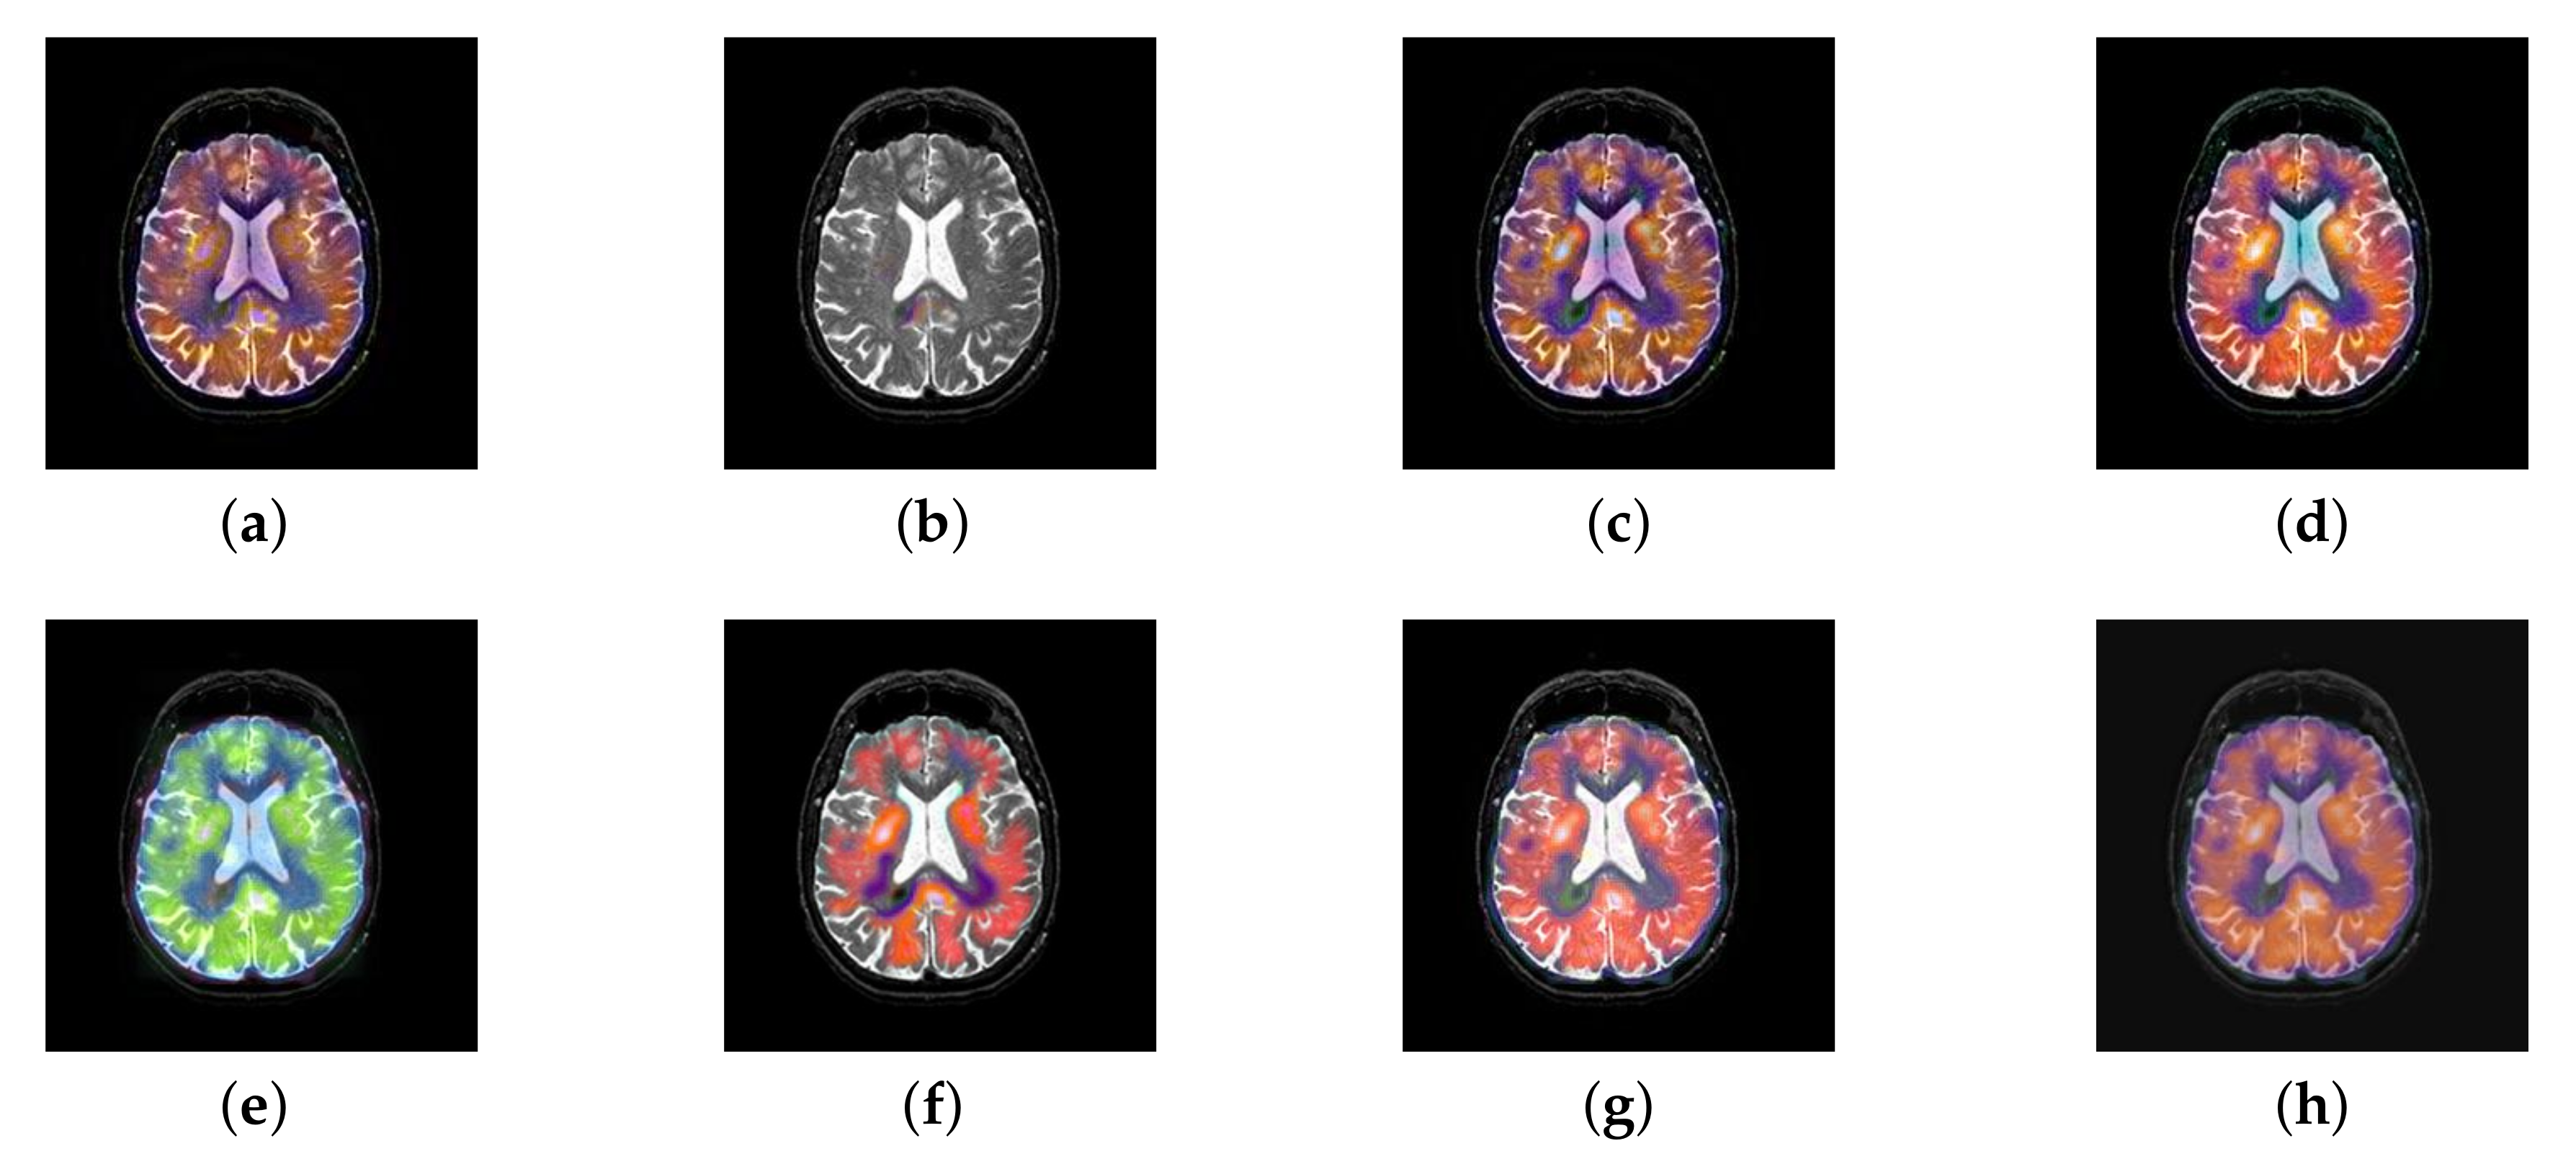

In this section, there are four multi-modal image sets and each set is consist of MRI image and SPECT image that are corresponding to the sanme location slice of the brain as shown in Figure 7. Among them, Figure 7e,f are captured from patients who have suffered a subacute stroke. Figure 7a–d,g,h are captured from patients who have brain tumor. The fused images with different fusion methods based on DTCWT, NSCT, GFF, LPSR, IGM, DDcGAN, FusionCNN, and the proposed methods are shown in Figure 8, Figure 9, Figure 10 and Figure 11. It can be seen that the fused images obtained by LPSR and FusionCNN algorithm have serious color distortion. Based on DTCWT and NSCT algorithm, the fusion image structure information is not obvious. The fused images obtained by GFF and IGM algorithm contain almost no color information, which is not conducive for doctors to make correct diagnosis. The image obtained by the DDcGAN algorithm saves the color information in the SPECT to a great extent; however, the brightness of the fused image is too large, which causes the image to have no sense of hierarchy and the contrast to decrease. By comparing with other algorithms, we find that our algorithm has good color retention effect, clear structure information, moderate brightness, and no artifacts.

Figure 7.

Four pairs of magnetic resonance imaging (MRI)-single-photon emission computed tomography (SPECT) source images: (a,c,e,g) are MRI images; (b,d,f,h) are SPECT images.

Figure 8.

Fused medical images obtained by different algorithms (Figure 7a,b): (a) dual tree complex wavelet transform (DTCWT), (b) guided filtering fusion (GFF), (c) non-subsampled contourlet transform (NSCT), (d) Laplacian pyramid sparse representation (LPSR), (e) internal generative mechanism (IGM), (f) Fusion convolutional neural network based (FusionCNN), (g) dual-discriminator conditional generative adversarial network based (DDcGAN), and (h) FusionNet.

Figure 9.

Fused medical images obtained by different algorithms (Figure 7c,d): (a) DTCWT, (b) GFF, (c) NSCT, (d) LPSR, (e) IGM, (f) FusionCNN, (g) DDcGAN, and (h) FusionNet.

Figure 10.

Fused medical images obtained by different algorithms (Figure 7e,f): (a) DTCWT, (b) GFF, (c) NSCT, (d) LPSR, (e) IGM, (f) FusionCNN, (g) DDcGAN, and (h) FusionNet.

Figure 11.

Fused medical images obtained by different algorithms (Figure 7g,h): (a) DTCWT, (b) GFF, (c) NSCT, (d) LPSR, (e) IGM, (f) FusionCNN, (g) DDcGAN, and (h) FusionNet.